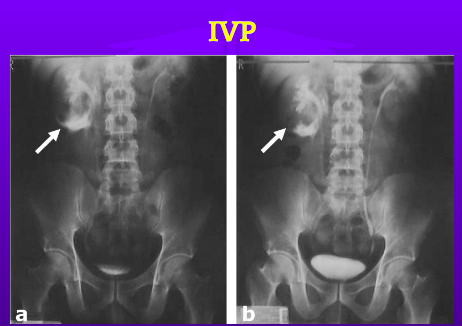

IVP